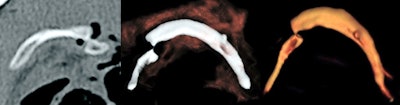

Between February 2016 and March 2019, Böven and her colleagues analyzed 112 fractures and injuries from 33 human cadavers (8 women, 25 men, with a mean age of 54 ± 18 years, range 31-92 years) that underwent whole-body postmortem CT after traumatic death. They reconstructed pathologies with CR and VR techniques, and classified fractures according to their dislocation.

Two forensic pathologists evaluated images according to their expressiveness and judicial relevance, and they decided whether CR reconstructions were suitable for judicial reviews. Two radiologists determined the detection rate of pathologies, and a traumatic cause of death was included.

CR was more expressive than VR for all three trauma categories (p < 0.01). Also, CR was more expressive than conventional CT when used for fractures with dislocation (p < 0.001), injuries of the ventral body surface (p < 0.001), and demonstration of foreign bodies (p = 0.033). CR and VR became more expressive with a higher grade of fracture dislocation (p < 0.001). In total, 20% of all pathologies in the CR and VR reconstructions were not detectable by radiologists.

"Due to the findings of our study, the use of CR for judicial reviews but also for other clinical demonstrations became the method of choice in our institute," Böven pointed out. "We also use CR reconstructions to demonstrate soft tissue injuries like stab wounds and penetration of foreign bodies more often than before."

- CR was more useful than conventional postmortem CT slices in cases of fractures with substantial dislocation, demonstration of foreign bodies, and body surface injuries not covered by other body parts or the CT table.